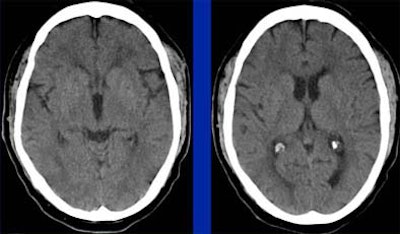

| Follow-up MRI (left, DWI or diffusion-weighted imaging; right, FLAIR technique) in the same elderly male patient shows that area of salvageable penumbra seen in initial CT was not saved, and the entire area has become infarcted. Questions relating to the patient's history of gastrointestinal bleeding led to initial decision to forgo tPA. Diffusion-weighted MRI identifies ischemic but living brain parenchyma at risk for infarction by assesssing the correlation between the diffusion abnormality and the MR perfusion abnormality. Images courtesy of Dr. Jay Cinnamon. |

| In this patient, "good old-fashioned" (GOF) head CT (left) depicts acute infarction in the left frontal lobe. Perfusion imaging was performed to assess the presence of penumbra. However, parametric color mapping shows substantially matched CBF and CBV, indicating infarcted tissue that is not salvageable. Images courtesy of Dr. Jay Cinnamon. |